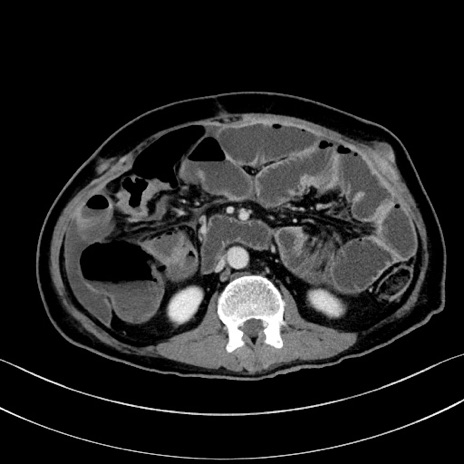

症例28(横断像)

【症例】60歳代男性

【主訴】嘔吐

【現病歴】胃癌にて胃全摘後。食思不振が悪化し、夜中に嘔吐することがある。

【既往歴】胃癌、胃全摘、脾摘、胆摘後

【データ】WBC 5900、CRP 10.56